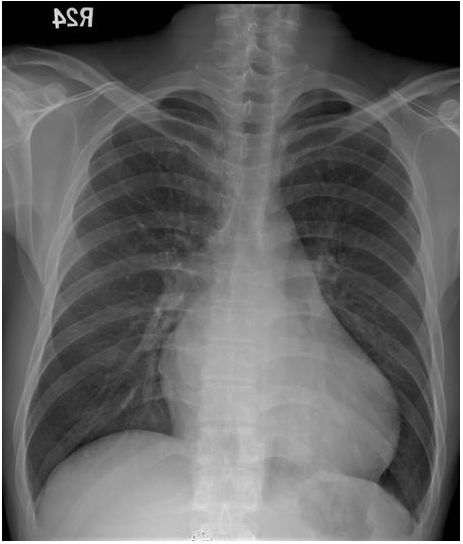

15. 病人是43歲生意人,經常出國經商,於五月十六日因有進展性呼吸困難乃至急診求醫,病人於五月三日旅行日本時突有忽冷忽熱,伴有乾咳呼吸困難及胸悶,且當時自量血壓只有90/60 mmHg¬,其後症狀稍解,乃回國休養,但在五月十四日運勳性呼吸困難逐漸轉劇.理學:血壓95/75 mmHg;心跳78/分,規則律跳;頸靜脈正常,但心臟顯著擴大,S1及S2都轉弱;都無心雜音,其他理學所見尚稱正常¬.病人有高血壓及高脂血及每天抽煙1.5包有三十年之久,且在1.5年前曾有短陣性腦缺血發作.,生化檢查:只有GOT 50u/L;GPT 25u/L;Troponin I(ng/ml), CK,(U/L)CK-MB(U/L):五月十六日 - 5.65,246,17.1;五月十七日- 3.74,190,10.1;胸部X光及心電圖 如示,請問下列何者是最有可能的診斷?

(A) 非ST上昇急性心肌梗塞症 (B) 心絞痛 (C) 心肌炎合併心肌病變 (D) 高血壓性心臟病 (E) 肺動脈血栓症